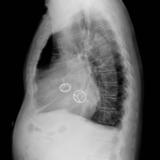

Ao valve calcif (lat only)

Date: 01/26/2009

Views: 2739